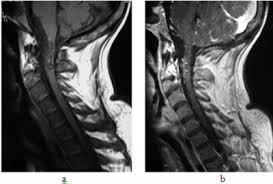

However, it can reveal nerve root enhancement and may be an effective diagnostic adjunct. The severity on mri does not correlate with severity of the clinical condition. Fisher syndrome, a clinical variant of guillain­ barre syndrome characterized by ataxia, are­ flexia, and ophthalmoplegia, brain stem lesions have been described with cranial mr.imaging (8). Its signs and symptoms are similar to those of other neurological disorders and may vary from person to person. Sagittal and axial post contrast t1 fs images shows smooth thickening and abnormal enhancement of the cauda equina and the ventral nerve roots. Moreover, gbs is also associated with any vaccination. Your doctor may then recommend: It is characterized by a triad of ophthalmoplegia, ataxia, and areflexia.

Clinical presentation is usually characterized by rapidly progressive, ascending, and symmetric paralysis of the extremities. Although no abnormalities were observed on brain and spinal magnetic resonance imaging and electroencephalography, peripheral nerve conduction velocity tests failed to evoke motor and sensory nerve action potentials. It is characterized by a triad of ophthalmoplegia, ataxia, and areflexia. Sagittal and axial post contrast t1 fs images shows smooth thickening and abnormal enhancement of the cauda equina and the ventral nerve roots. Scott olson / staff / getty images Moreover, gbs is also associated with any vaccination. Your doctor may then recommend: Mri is sensitive, but nonspecific, for diagnosis. The study findings are published in the journal neurological research. Mr imaging findings in eight patients (three male, five female; Immune checkpoint inhibitors (icis) have been increasingly used in the treatment of various types of tumors with favorable results. The most common result is a weakness and numbness that starts at the tips of the fingers and toes and spreads inward toward the body. Guillain barré syndrome (gbs) is characterized by demyelination and axonal degeneration of peripheral nerves.

On csf analysis, the cell count is normal in 85% of patients, and high protein values are seen in 64%. Sagittal and axial post contrast t1 fs images shows smooth thickening and abnormal enhancement of the cauda equina and the ventral nerve roots. Clinical presentation is usually characterized by rapidly progressive, ascending, and symmetric paralysis of the extremities. Fisher syndrome, a clinical variant of guillain­ barre syndrome characterized by ataxia, are­ flexia, and ophthalmoplegia, brain stem lesions have been described with cranial mr.imaging (8). Typically, both sides of the body are involved, and the initial symptoms are changes in sensation or pain often in the back along with muscle weakness, beginning in the feet and hands, often spreading to the arms and upper body. Mr imaging findings in eight patients (three male, five female; With treatment, people may improve more quickly. However, it can reveal nerve root enhancement and may be an effective diagnostic adjunct. Your doctor may then recommend: The most common result is a weakness and numbness that starts at the tips of the fingers and toes and spreads inward toward the body. Moreover, gbs is also associated with any vaccination. Mri is sensitive, but nonspecific, for diagnosis. Immune checkpoint inhibitors (icis) have been increasingly used in the treatment of various types of tumors with favorable results.

Typically, both sides of the body are involved, and the initial symptoms are changes in sensation or pain often in the back along with muscle weakness, beginning in the feet and hands, often spreading to the arms and upper body. Sagittal and axial post contrast t1 fs images shows smooth thickening and abnormal enhancement of the cauda equina and the ventral nerve roots. The diagnosis is usually established on the basis of symptoms and signs, aided by cerebrospinal fluid findings and electrophysiologic criteria. Both ms and gbs are autoimmune. The severity on mri does not correlate with severity of the clinical condition. Although no abnormalities were observed on brain and spinal magnetic resonance imaging and electroencephalography, peripheral nerve conduction velocity tests failed to evoke motor and sensory nerve action potentials. On csf analysis, the cell count is normal in 85% of patients, and high protein values are seen in 64%. Mri is sensitive, but nonspecific, for diagnosis. It is the most common cause of rapidly progressive flaccid paralysis. The most common result is a weakness and numbness that starts at the tips of the fingers and toes and spreads inward toward the body. The study findings are published in the journal neurological research. 1 article features images from this case 14 public playlist includes this case Mr imaging findings in eight patients (three male, five female;